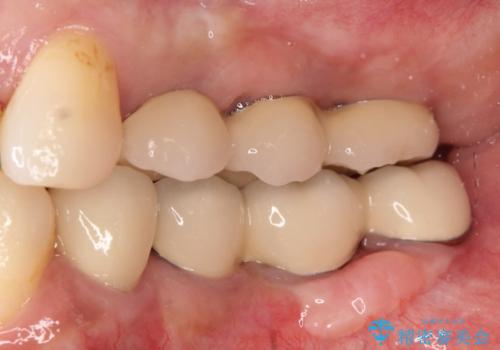

- 奥歯が欠損していることを主訴に来院されました。

インプラントにて補綴治療を行なっております。

綺麗になり、しっかり噛めるようになったと満足していただきました。